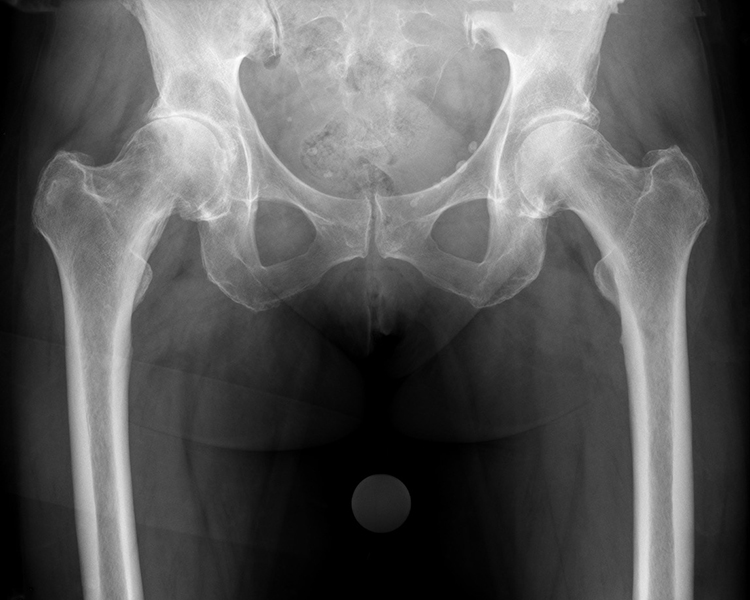

CAD-gestützte Planung

Nach meiner Überzeugung kann nicht jeder Patient mit einem einzigen Prothesenmodell erfolgreich versorgt werden. Daher arbeite ich seit vielen Jahren mit verschiedenen bewährten Prothesenmodellen, um nahezu jede individuelle Anatomie optimal abzubilden.

Nur durch diese maßgeschneiderte Auswahl können die Muskeln wieder in ihrer natürlichen Funktion arbeiten,  die Voraussetzung für schmerzfreies Gehen und bestmögliche Lebensqualität.

Die computergestützte (CAD) Planung ermöglicht es, jeden Eingriff präzise zu simulieren und die optimale Prothese für Ihre individuelle Anatomie auszuwählen, für maximale Präzision und langfristig erfolgreiche Ergebnisse.

computergestützte OP-Planung für optimale Ergebnisse:

• Patientenspezifische Anatomieanalyse

• Präzise Implantatauswahl & -positionierung

• Simulation von Offset, Beinlänge & Gelenkzentrum

• Biomechanisch optimierte Rekonstruktion

Anamnesegespräch, klinische Untersuchung, Bildgebung (Röntgen/ggf. MRT), Prüfung konservativer Alternativen

• OP-Tag: Implantation der Prothese, Röntgenkontrolle noch im OP (Teilaufnahme der Hüfte)

• Röntgenkontrolle vor Entlassung (Hüftübersichtsaufnahme, Bemessung der Biomechanik)